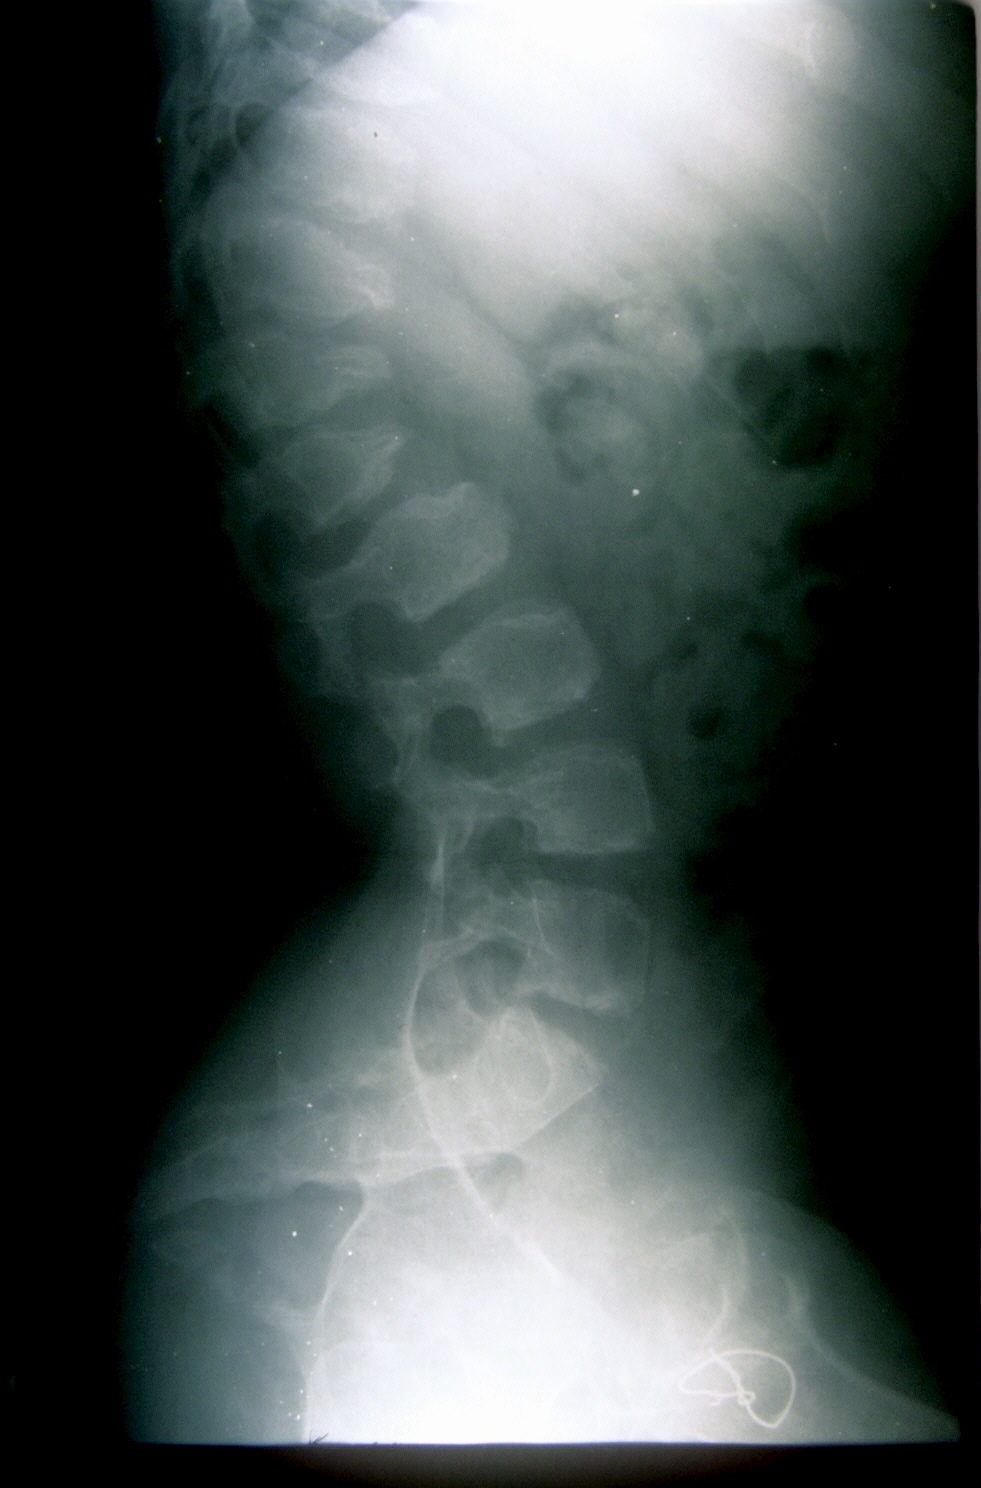

Seudoacondroplasia. [Pseudoachondroplasia]